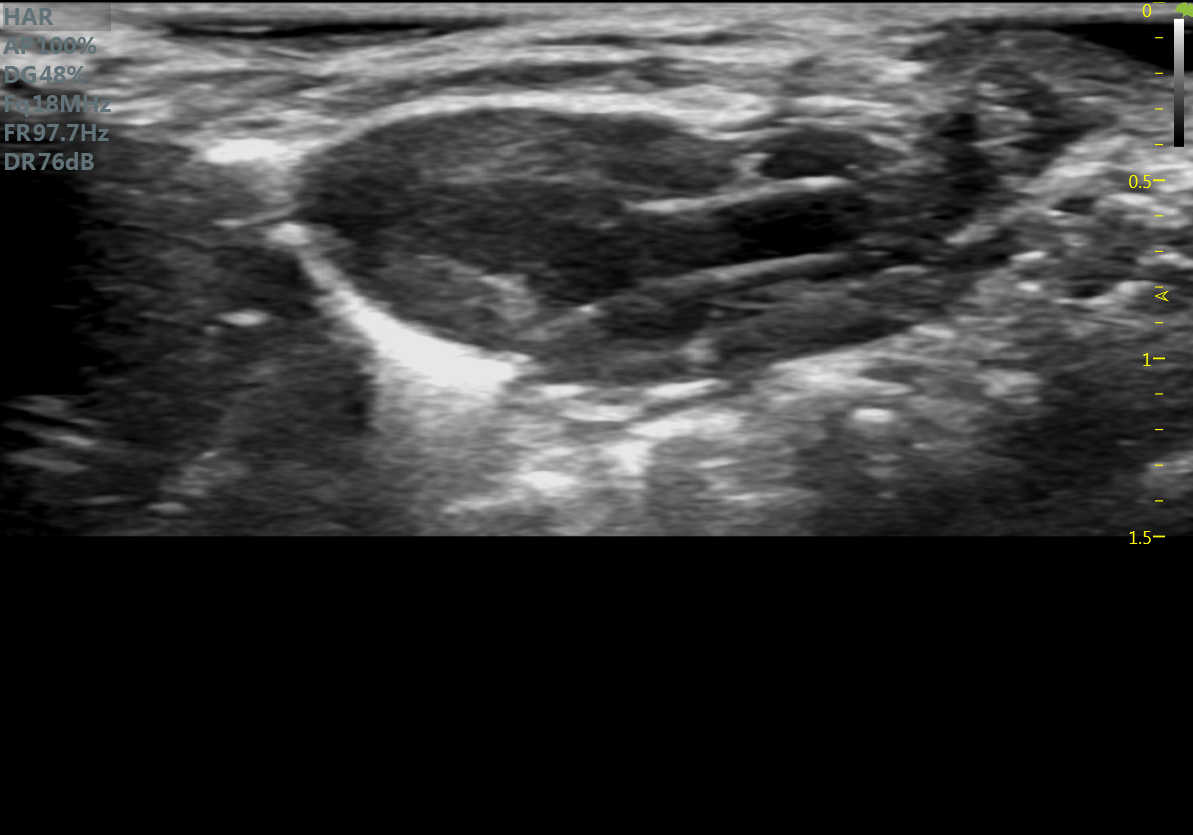

小鼠长轴B型 小鼠短轴B型

大鼠长轴B型 大鼠主动脉弓